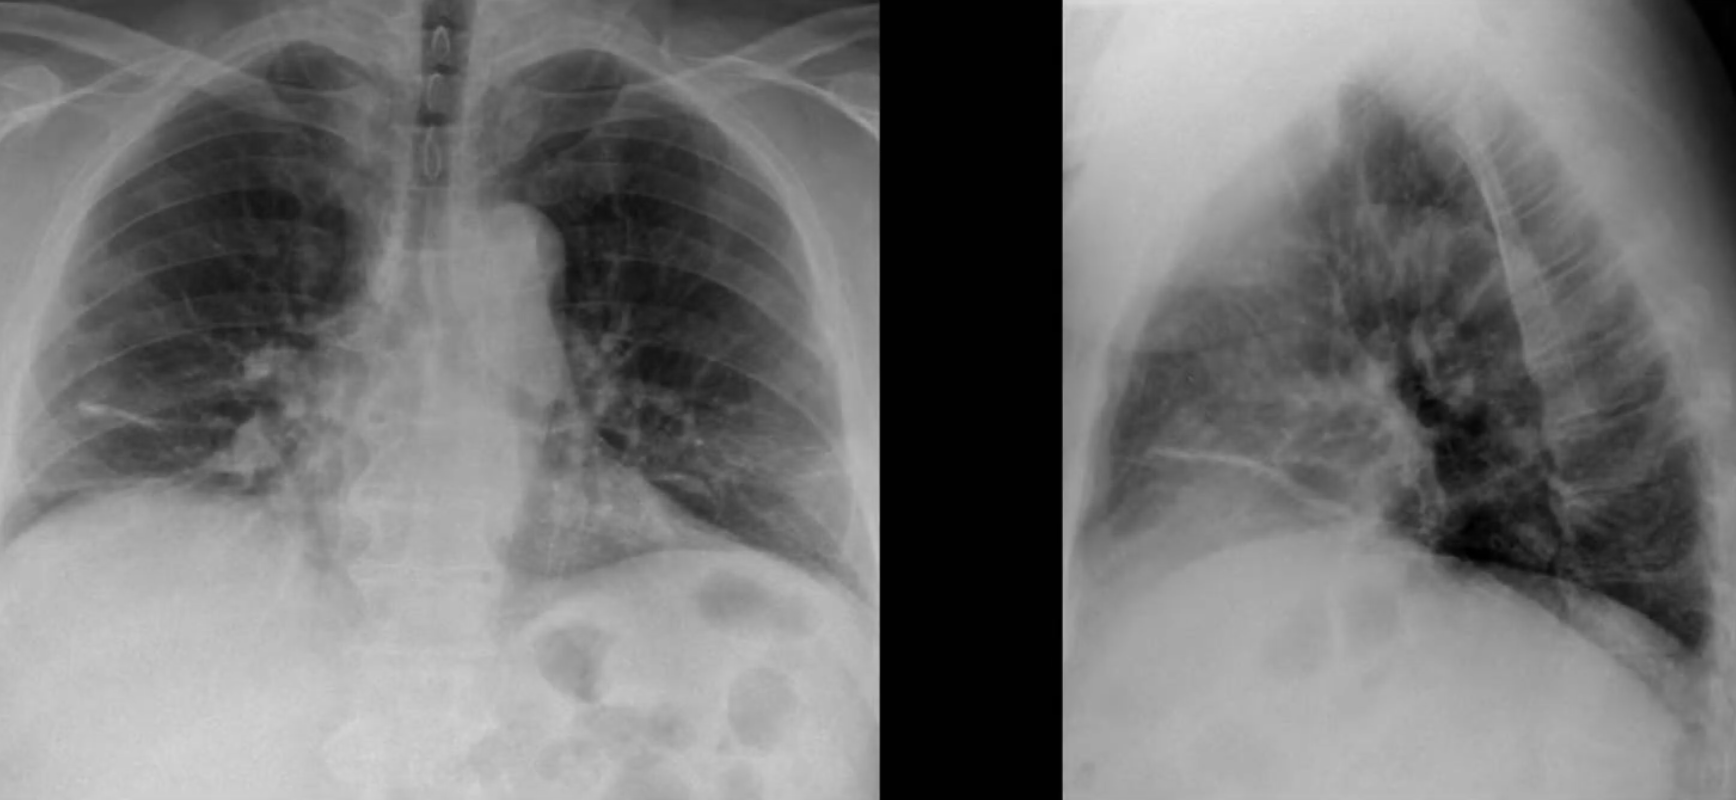

Cardiac Silhouette and Mediastinum

- Widened mediastinum is defined as >8cm.

Hilar Enlargement — Differentials

- Malignancy: primary lung cancer, lymphoma, metastatic disease

- Infection: tuberculosis, viruses (e.g. EBV)

- Other: sarcoidosis, silicosis, pulmonary hypertension, pulmonary artery aneurysm, bronchogenic cyst

Other

- Pneumomediastinum

- Pneumopericardium